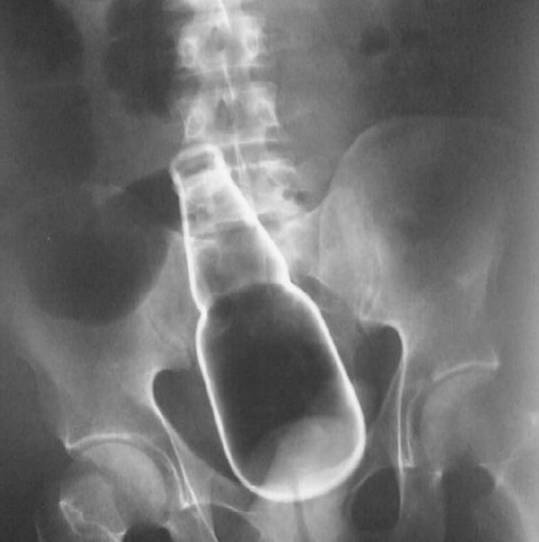

前3种原因是很难人为避免的,但第4种是需要专门挑出来说的。为什么呢?我知道一些男性会特别喜欢往菊花里面塞东西,比如啤酒瓶、乒乓球、假丁丁、手机、电灯泡……对于这些男性而言,他们的菊花就像哆啦A梦的口袋似的,藏有无穷无尽的宝藏……

这些主动向菊花内部输入物品的行为,非常容易导致肛管直肠环损伤,导致括约肌失去括约功能而至大便失禁。即便是较为常见的G交,如果姿势不对或用力太猛,也可能导致括约肌损伤。所以,我们经常说性行为需要“安全语”,就是在啪啪啪的过程中,如果一方难以忍受,一定要及时叫停!

图片来源:[1]刘志强, 颜国正, 克磊, 翁晓靖. 新一代反馈式人工肛门括约肌系统的研究. 仪器仪表学报 Chinese Journal of Scientific Instrument. Vol.34 No.5, May, 2013.